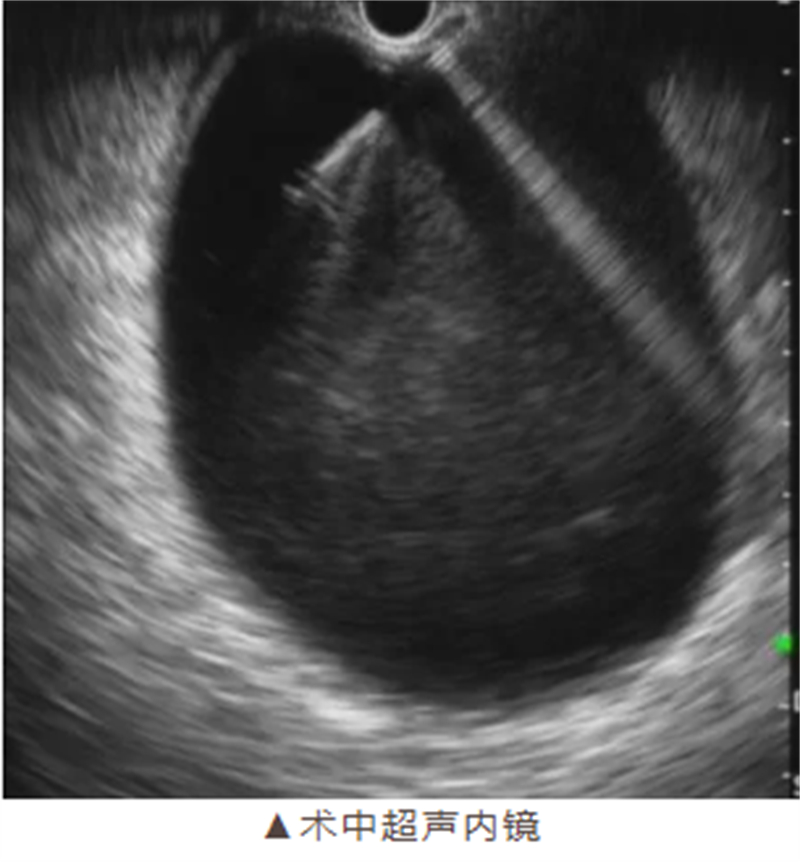

手术如期进行,在麻醉科团队的密切配合下,消化病肝胆胰疾病诊疗中心手术团队娴熟地操作超声内镜,准确定位囊肿位置,避开重要血管和器官,成功完成穿刺引流并植入支架。整个手术过程仅耗时约40分钟,术中无出血,展现了柳州市人民医院医疗团队高超的技术水平和专业素养。

超声内镜引导下的穿刺引流术则具有独特优势。它利用实时超声引导,精准定位囊肿位置,避开重要血管和器官,通过自然腔道入路进行穿刺引流,体表无创口,大大降低了手术风险和患者的痛苦。同时,留置支架还能显著降低复发率,使患者术后能够迅速恢复进食和正常生活。